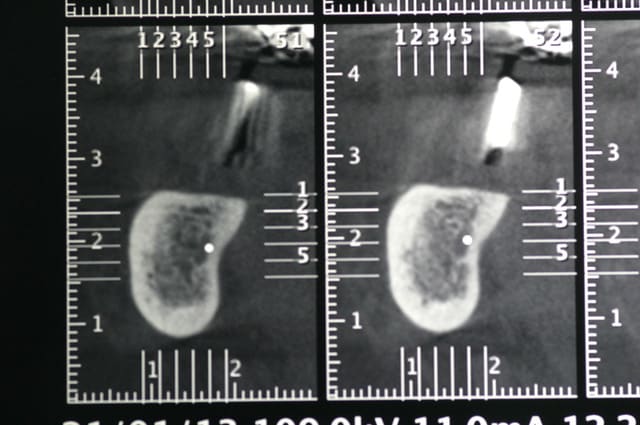

ci joint les photos des coupes scanner d'un patient à qui j'ai proposé de poser un implant afin de remplacer la 36. sur les coupes, on vois nettement le dédoublement du NAI.

tient pour revenir sur ce que disait Pxav, sur une image comme celle ci, vous passeriez en vestibulaire? c'est vrai qu'il y a de la place, mais je n'ai pas osé...

voila, j’espère que c'est lisible.